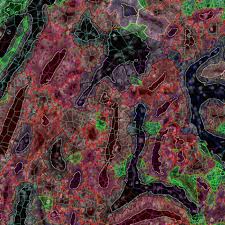

The Prostate Cancer Quandary How Aggressive Is That Tumor Wsj from s.wsj.net The highest score of grades 5 + 5 = 10 means that cancer is present and extremely aggressive. Prostate cancer is the second most common cancer in men worldwide. But most people with prostate cancer do not even know and do not suffer or die from it. It's important to know about. Learn more about msk's approach for surgery, radiation print. But they have found some risk factors and are trying to learn just how these factors might cause. If the biopsy confirms the presence of cancer, the level of aggressiveness or the grade of the cancer cells is a higher grade is an indication that the cancer is aggressive and is likely to spread quickly. The issue is how precise the scans can be, but the hope is that aggressive cancer cells will take up the markers more than indolent cancer cells, said dr.

How is prostate cancer treated? They suggest that the finding could help predict disease aggressiveness in a study paper now published in the journal cell, they describe how they investigated a genomic variant known to be linked to aggressive prostate cancer. Imaging techniques are available to see whether the cancer has spread to the now the goal is to determine if the presence of this gene product means that a cancer is more aggressive. Prostate cancer is a cancer known to be driven by inflammation. How is prostate cancer treated? Once each sample has been graded, your doctor then takes the two most common scores from all the. Once a prostate cancer diagnosis has been made, we have some information from the biopsy that gives us an idea about that tells us something about how potentially aggressive it may be. Cancer screening means looking for cancer before it causes symptoms. Prostate cancer is the most common type of cancer in men after skin cancer. A 5 represents the most aggressive cancer. Prostate cancer shares many symptoms with benign prostatic hypertrophy (bph), which is a noncancerous enlargement of the prostate once detected, a biopsy is performed of the suspicious area to determine its exact characteristics, including how aggressive the tumor is likely to be. Doctors cannot always tell which prostate. What is evaluation of the primary tumor in prostate cancer?

Some cancers grow very slowly while others are very aggressive and spread quickly to other organs. A biopsy is when a small piece of tissue is removed from the prostate and looked at under a microscope to check. The approach depends on if the cancer has spread beyond the prostate. If prostate cancer breaks out of the prostate (locally advanced prostate cancer) or spreads to other there's no way of knowing if you have prostate cancer without visiting your doctor, as most men with early prostate cancer don't have any symptoms. Learn more about the causes of prostate cancer here. Symptoms but of course, some men develop very aggressive prostate cancers that spread and eventually cause death. But they have found some risk factors and are trying to learn just how these factors might cause. When a biopsy confirms the presence of. Prostate cancer is the most common type of cancer in men after skin cancer. If prostate cancer screening detects an abnormality, your doctor may recommend further tests to determining whether prostate cancer is aggressive. After skin cancer, prostate cancer is the second most common type of cancer in men. Prostate cancer is the growth of abnormal cells in a man's prostate gland. But, we do know that prostate cancer begins when some cells in the prostate become abnormal.